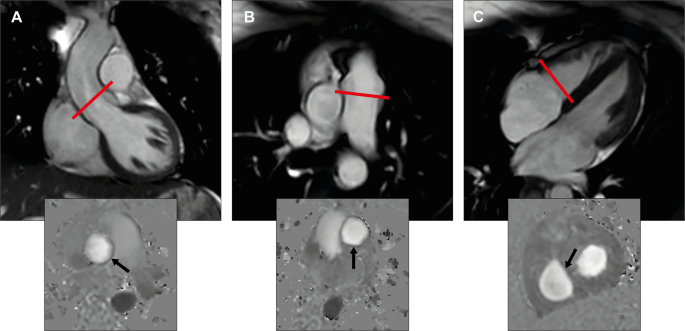

Flow volume quantification of the aortic (AoFF) and the pulmonary forward flow (PuFF) as well as the tricuspid inflow (TrIF) was performed using through-plane phase contrast (PC) velocity encoded sequences (repetition time 4.8 ms, echo time 2.9 ms, flip angle 12°, 40 phases per cardiac cycle, echo train length 3, field of view 320 × 260 mm, voxel size 2.5 × 2.5 mm, slice thickness 8 mm) with retrospective ECG gating during gentle expiratory breath-hold for approximately 12–16 s according to the standard BH protocol. The PC images were acquired perpendicularly aligned to the direction of the blood flow in two imaging planes in the aortic root at the level of the sinotubular junction in end-diastole and the main pulmonary artery just above the pulmonary valve (Fig. 1). AoFF was evaluated as an internal precision control to PuFF. In a previous study we have demonstrated high feasibility and reproducibility in the mitral position and in the present study the similar approach was applied to the flow quantification in the tricuspid position5,6. PC images were acquired perpendicularly aligned to the direction of the blood flow of tricuspid inflow in three orthogonal planes (4 chamber, 2 chamber and inflow-outflow views of the RV) approximately 1 cm below the tricuspid annulus in early diastole (Fig. 1)7. Flow volume quantification was also performed during FB for in average approximately 3 min during gentle free respiration (averaged 24 acquisitions phase-matched to ECG). PC images were acquired twice during BH at all valve positions with an optimized VENC (results are presented as the mean of the two independent measurements) and once during FB in the same position of each valve as during the BH approach. No special software is needed for the acquisitions. The initial velocity encoding (VENC) level was estimated based on echocardiographic information and was subsequently optimized, either in the presence of aliasing or when the difference between the initially set VENC and the determined maximal velocity was > 25%8. In the aortic and pulmonary position, the VENC was optimized during systole, whereas in the tricuspid position during diastole. Aliasing occurs in tricuspid valve during systole due to higher regurgitant velocity compared with inflow velocity. The potential for background phase offset errors was reduced by ensuring that the region of interest (ROI) in the imaging slice was for all PC sequences aligned in the isocenter of the magnet to minimize magnetic field inhomogeneities5. In all flow quantification, effective compensation for background phase offset was applied using adaptive image filtering. The background phase offset error after compensation was below the current limit of acceptance, i e < 0.6 cm/s, in all PC images of the present study9.

Image acquisition and analysis for CMR flow volume quantification. (A, B) Left and right ventricular outflow tract view in end-diastole. The red line illustrates the slice position for through plane phase contrast velocity imaging. Quantification of aorta and pulmonary flow is depicted in the corresponding phase contrast image below (arrow). (C) Four -chamber view in early diastole with an open tricuspid valve. The red line illustrates the slice position for through plane phase contrast velocity imaging. The corresponding phase contrast image for tricuspid inflow quantification in diastole is shown below (arrow).